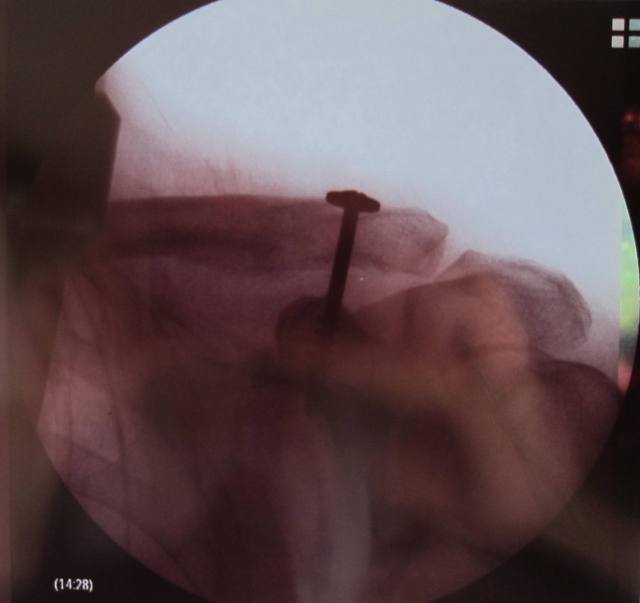

Doc says I did a ‘bang-up’ job of tearing all 6 ligaments. As bad as it gets before things start going SNAP. He’s happy with the work and the prognosis is good. Screw should come out in CORRECTION – 3 MONTHS. Then a little more sling time and back to work. Golf game should be tuned up in time for The TYMI at Pebble next year.